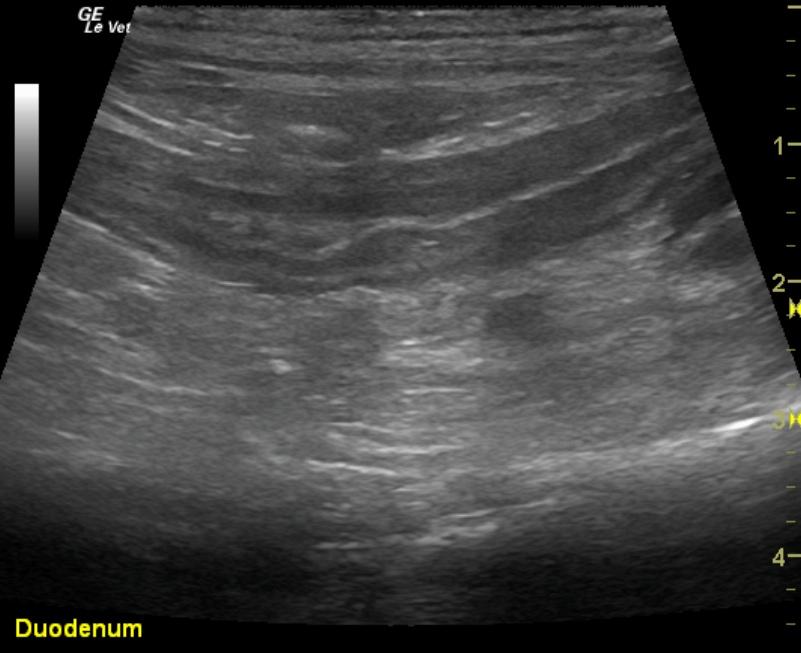

Pyloric outflow was mildly prominent in this patient with hypertrophy of the muscularis and mildly increased echogenicity of the submucosa layer. The remainder of the intestinal tract revealed thickened submucosal layers. Jejunal lymph nodes were enlarged at 2.87 x 1.47 cm with uniform contour, and the egg shape formation would be more suggestive of reactive lymphadenitis.